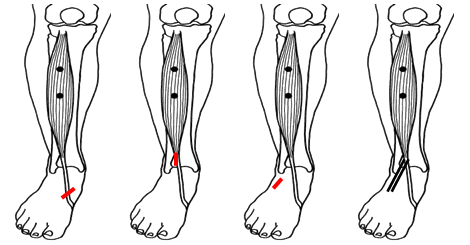

Calcaneus osteotomie

Bij een calcaneus osteotomie wordt het hielbot doorgezaagd en meer naar de buitenzijde verplaatst. De achtervoet komt zo meer van de “O” positie in een “X” positie.

Het vastzetten van beide botdelen gebeurt meestal met een schroef vanuit de hiel, middels een apart litteken.

Figuur 1: Voorbeeld van een calcaneus osteotomie. H=hielbot (calcaneus). De witte streep op het linker plaatje is de locatie van het litteken. De Rode pijl wijst naar de schroef. Op het meest rechtse plaatje zie je de verschuiving van het hielbot naar de buitenzijde